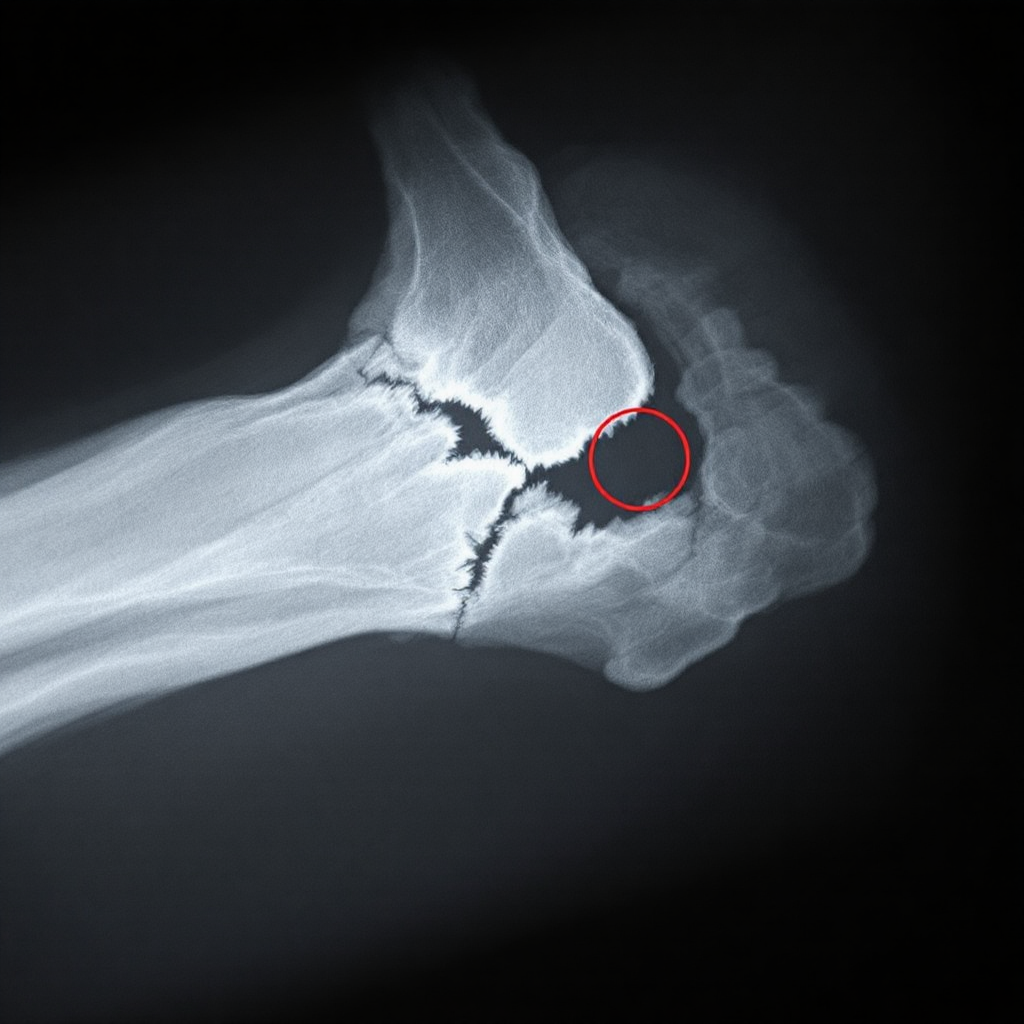

골절은 뼈의 구조가 파괴되어 금이 가거나 완전히 분리된 상태를 말해요. 외부 충격에 의해 발생할 수 있지만, 뼈가 약해진 상태에서도 쉽게 발생할 수 있죠. 일반적으로는 뼈가 부러졌다는 표현을 쓰지만, 의학적으로는 '골절'이라고 해요.

골절은 크게 두 가지로 나뉘어요. 하나는 '폐쇄성 골절'로, 피부는 멀쩡하지만 뼈 내부에 손상이 있는 경우예요. 또 하나는 '개방성 골절'인데, 뼈가 피부를 뚫고 나와 출혈이 동반되거나 감염 위험이 높은 상태를 말해요.

이외에도 금이 간 '균열골절', 뼈 조각이 여러 개로 부서진 '분쇄골절', 뼈가 끼거나 압축돼 일어난 '압박골절', 어린이에게 자주 나타나는 '녹지 않은 나뭇가지형 골절(유연 골절)' 등 다양한 종류가 존재해요.

눈으로 봐서 뼈가 튀어나오지 않더라도 부기, 멍, 압통, 움직일 수 없음 같은 증상이 있다면 골절일 가능성이 높아요. 무조건 병원에 가서 엑스레이나 CT로 확인하는 게 제일 안전해요!

A1. 일반적으로 엑스레이(X-ray)로 확인하지만, 경우에 따라 CT나 MRI가 추가될 수 있어요.